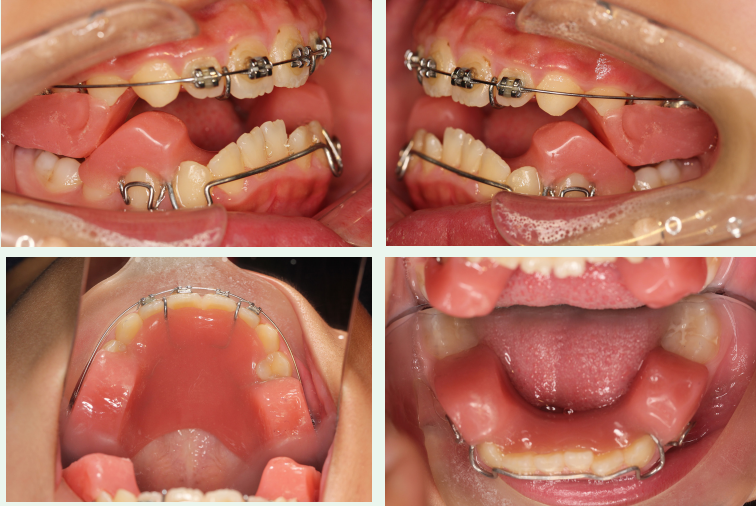

Twin-Block矫治器的结构分为上下两个咬合板,那么我们在制作Twin-Block的时候,给患者采蜡颌记录,通常采4-5毫米的蜡颌记录,为什么是这个高度呢?

因为我们正常都有息止颌位,也就是大家放松状态下,是半张嘴牙分开的咬合状态,这就叫做息止颌位,那息止颌位在后牙区就是4毫米。

所以在做Twin-Block双颌板的时候,蜡颌记录的厚度就应该要大于4毫米,当后牙的颌板的厚度大于4毫米的时候,它超过了息止颌位,下颌咀嚼肌就会被拉伸,而当咀嚼肌拉伸的时候,会产生主动性收缩的力量。

那么颌板把这个收缩的力量就传导到牙齿,就会对上下磨牙产生压入的力量,抑制后牙萌出,如此保存上下颌差异性生长产生的颌间间隙,颌间间隙能够促进下颌逆时针旋转,下颌颏部前移。

临床注意:Twin-Block 矫治器的上、下颌部分是分开的,孩子要能自由地前伸下颌,使下颌颌垫位于上颌颌垫前方。如果不能,一般是因为颌垫过高或前伸量过大,可通过调磨来解决。必要时,重新取咬合记录,减小后牙开合和下颌前移量。